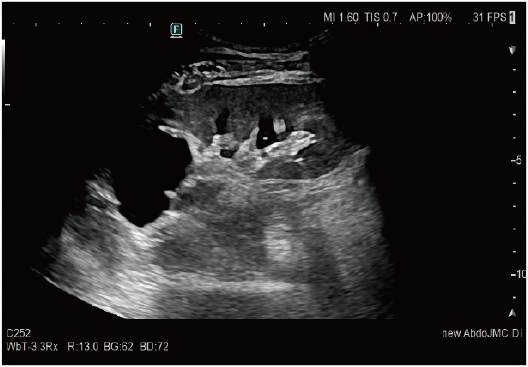

High visibility is realized in observation area. DeepInsight Technology, which used AI technology*1 in the development of image processing, is evolved to distinguish electrical noises and extract more tissue information so that images with rich gradation can be provided.

In addition to the sensitivity improvement, homogenous images can be acquired with high resolution in wider area of display. It is expected to prevent the overlook of information in wide area observations. eFocusing PLUS has enhanced tissue delineation performance as a result of its transmission beam design change and evolution of receiving technology.